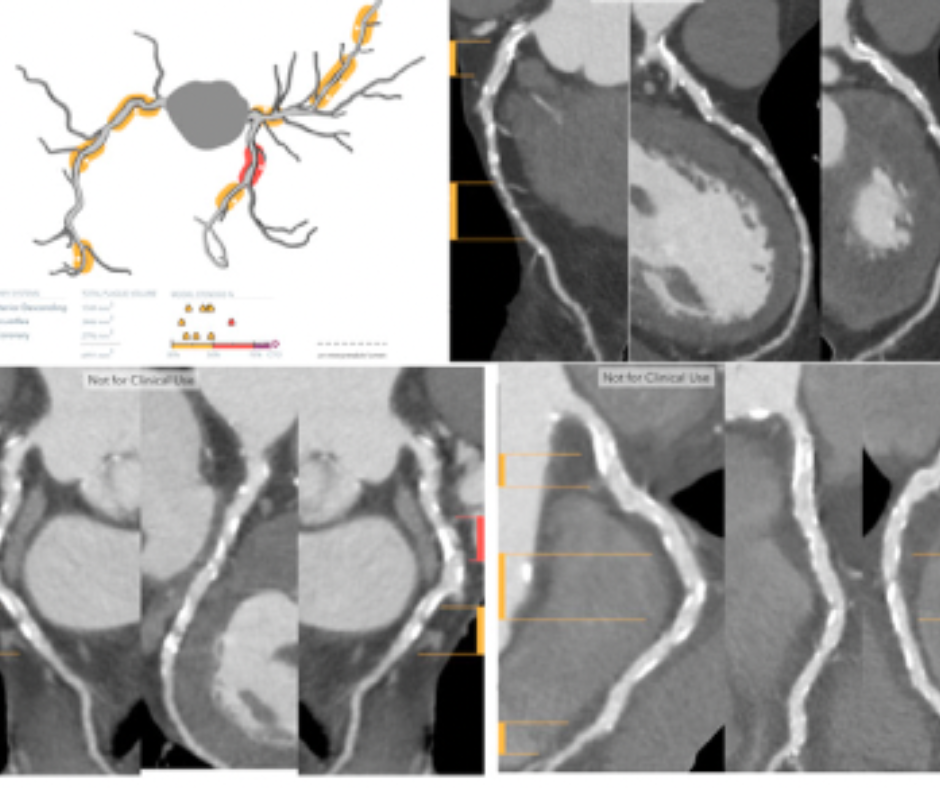

The automated measurement of heart ventricle diameters and detection of potential dilation in the right ventricle may facilitate quicker intervention in cases of pulmonary embolism.